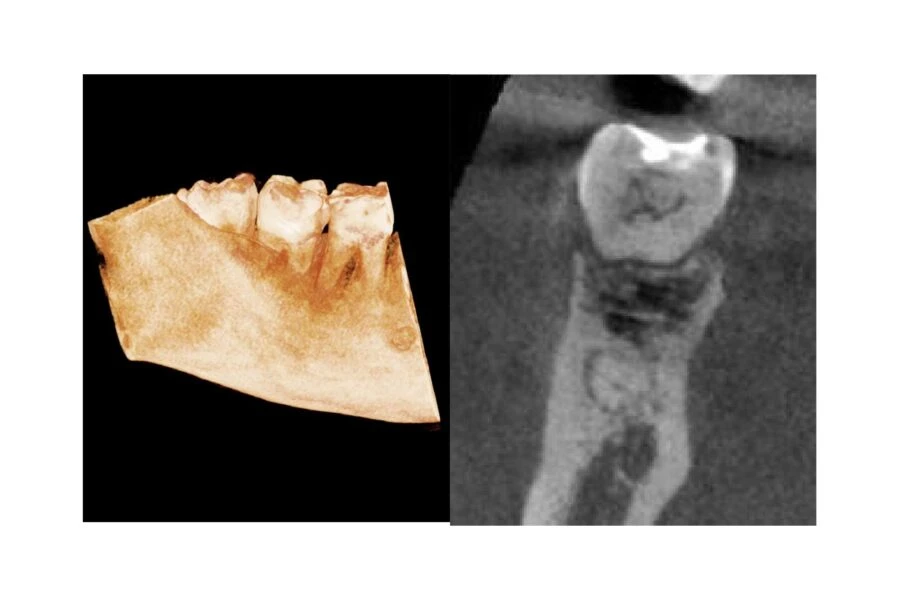

Răng cối số 8 hàm dưới bị va đập, các chóp không gần với ống tủy hàm dưới. Có một khoảng không mở rộng, không có hình dạng điển hình của một nang. Vấn đề này cũng có thể là do các đợt viêm nha chu trong quá khứ.

Lát cắt toàn cảnh của Răng cối hàm dưới từ số 6-8 và mặt cắt ngang của vùng LR6 cho thấy ống tủy, chiều rộng dây chằng nha chu bình thường và lớp màng cứng. Cũng có thể thấy không gian nang mở rộng liên quan đến LR8.

Ảnh toàn cảnh được cắt của LR6-8 hiển thị các viên sỏi tủy trong LR6, LR7 và LR8.